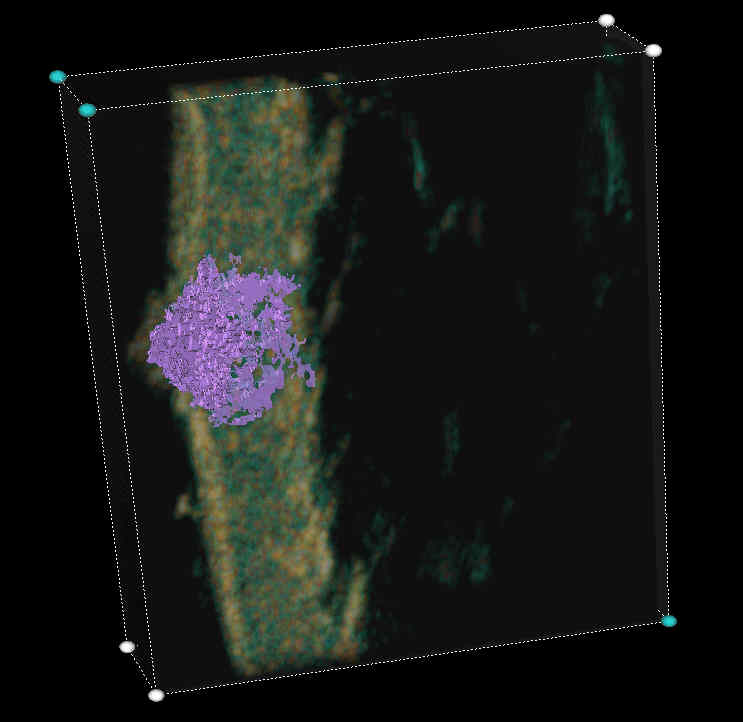

20 MHz 3D images

| Misc. |  Cellulite, arm |

Microdialysis tube |

Intradermal nevus |

Highlight. intrad. nevus |